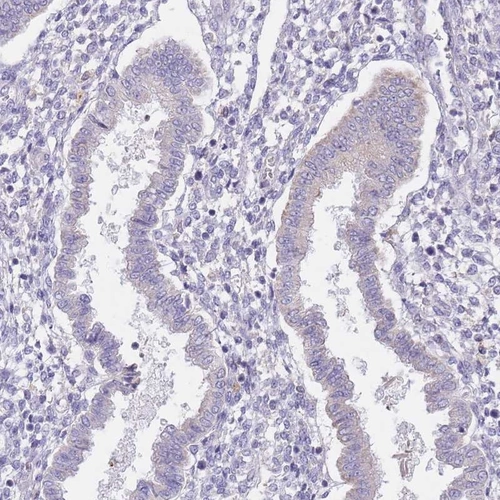

Immunohistochemistry analysis in human epididymis and endometrium tissues using Anti-AP1S2 antibody. Corresponding AP1S2 RNA-seq data are presented for the same tissues.